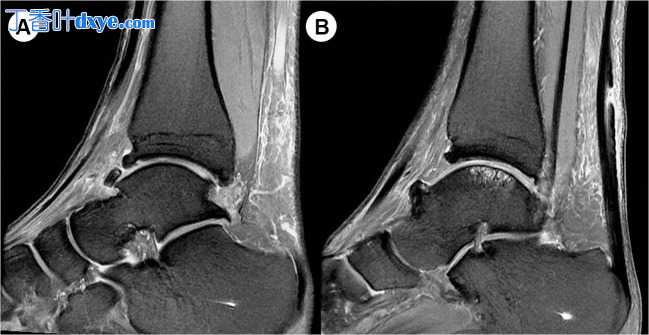

踝关节韧带重建术后 5 个月的患者随访   图 3

(A、B)术前影像学检查难以诊断的骨软骨病变。